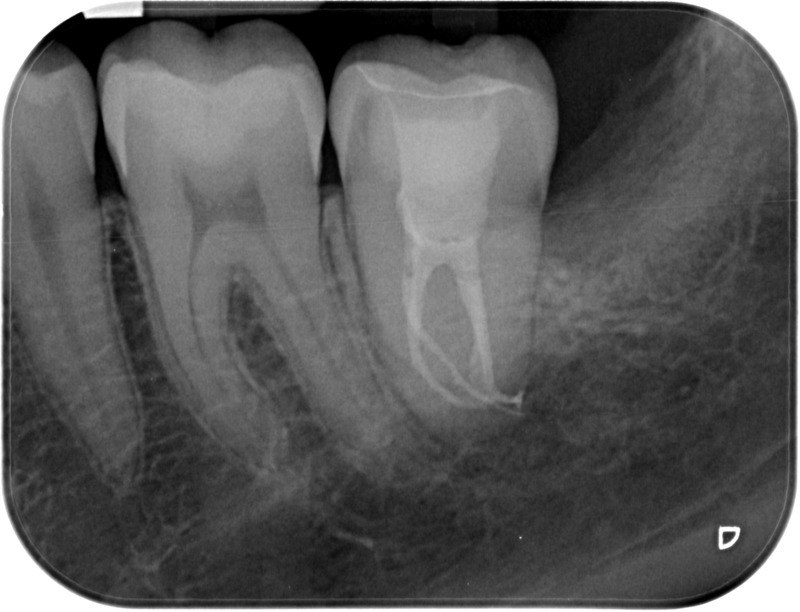

• Reprise de traitement endodontique : La manœuvre consiste à retourner à l’intérieur des racines d’une dent déjà traitée. Il arrive occasionnellement qu’une nouvelle inflammation se déclare suite à une reprise de carie ou une fracture de la dent, ou si le premier traitement endodontique est incomplet. Après s’être assuré que la dent lésée était conservable, il convient de désinfecter de nouveau le réseau canalaire parfois très complexe. La nouvelle obturation des canaux devra être protégée aussi rapidement que possible pour éviter une éventuelle contamination bactérienne.

Avant